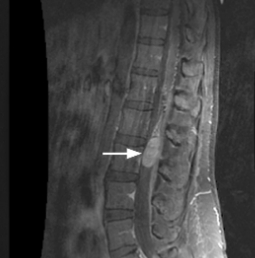

脊髓里面有个小肿瘤可以手术吗?脊髓里面的小肿瘤是可以手术的,脊髓里面的小肿瘤属于脊髓肿瘤。脊髓肿瘤起源于髓内或脊髓周围细胞,当神经根受脊髓肿瘤压迫可引起疼痛、麻木、针刺感、神经所支配的肌肉乏力和沿着神经的放射痛。疼痛可能沿神经根受压的神经蔓延。如果持续压迫,累及肌肉可能会萎缩,可能出现行走困难。

针对脊髓肿瘤的治疗,在国内外,手术切除一直是优选。理想情况下,脊柱肿瘤手术治疗的目标是完全消除肿瘤,但这一目标可能具有复杂的风险,长期性损害脊髓和周围神经。医生需考虑到患者的年龄和整体健康。在确定治疗方案时,还需考虑肿瘤的类型,以及它是否起源的位置,或是否已从你身体的其他部位扩散到你的脊柱。

由于脊髓肿瘤位置深在,周围有许多神经组织,手术时容易造成损伤,所以做脊髓肿瘤手术时,不同的神经显微镜、神经导航设备、术中核磁等高复杂辅助设备是重要的,它们可以帮助手术医生更好、更顺利的手术。另外除了前沿的手术技术、设备,主刀医生才是手术成功的关键,因为不管技术、设备多么前沿,始终是工具,而这个工具的操作者就是医生,只有经验丰富、技术高超的医生才能确定顺利的同时确定切除率。